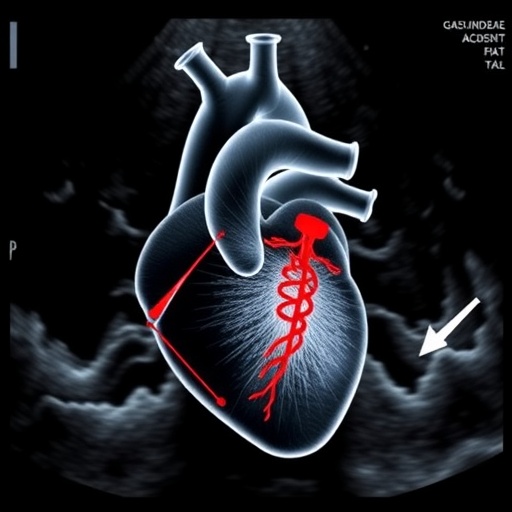

Addressing these critical limitations, the current study introduces an innovative ultrasound-guided percutaneous left heart injection (ULI) technique. This method harnesses the precision of ultrasound imaging to guide the injection process in real-time, thereby enhancing the safety profile and ensuring targeted delivery to the thoracic aorta with minimal collateral damage.

This ultrasound-guided technique utilizes high-resolution imaging to visualize cardiac structures during injection, allowing for precise needle placement into the left ventricle. By honing in on the left heart region, ULI leverages immediate proximity to the ascending thoracic aorta, facilitating efficient vector dispersal directly to the target tissue with limited systemic spillover.